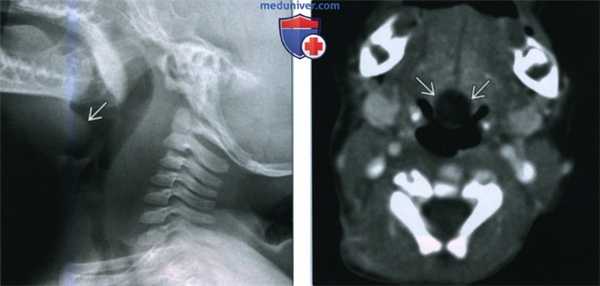

(Слева) На рентгенограмме в боковой проекции, выполненной ребенку со стридором, в проекции корня языка определяется тень с ровным краем, распространяющаяся в валлекулу, по интенсивности соответствующая мягким тканям.

(Справа) При аксиальной КТ с КУ в корне языка по средней линии визуализируется гиподенсная киста с ровными краями, не накапливающая контраст. На основании данных КТ образование нельзя достоверно дифференцировать с кистой щитоязычного протока, расположенной в области слепого отверстия.